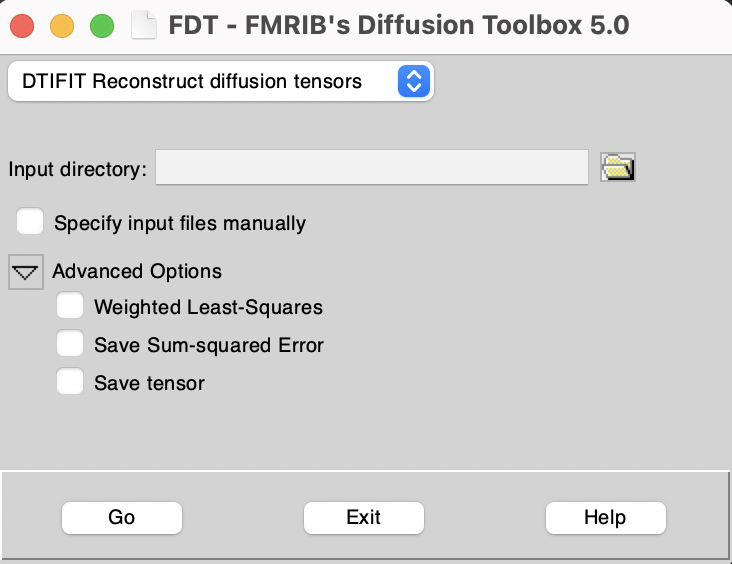

Graphical interface

Alternatively, in the FDT GUI, use the top left drop down menu to select "DTIFIT Reconstruct diffusion tensors".

In addition to the required input above, the user can choose to apply a weighted least-squares regression instead of the default standard linear regression. The user can also choose to save the tensor elements and/or the sum of squared error. This last output can be useful for detecting artefacts.

Tip! On the FDT GUI, you can specify an input directory containing all the required files with standardized filenames, or alternatively you can specify input files manually by turning on the "Specify input files manually" switch. If an input directory is specified then all files must be named as shown in parentheses above. If input files are specified manually they can have any filename.